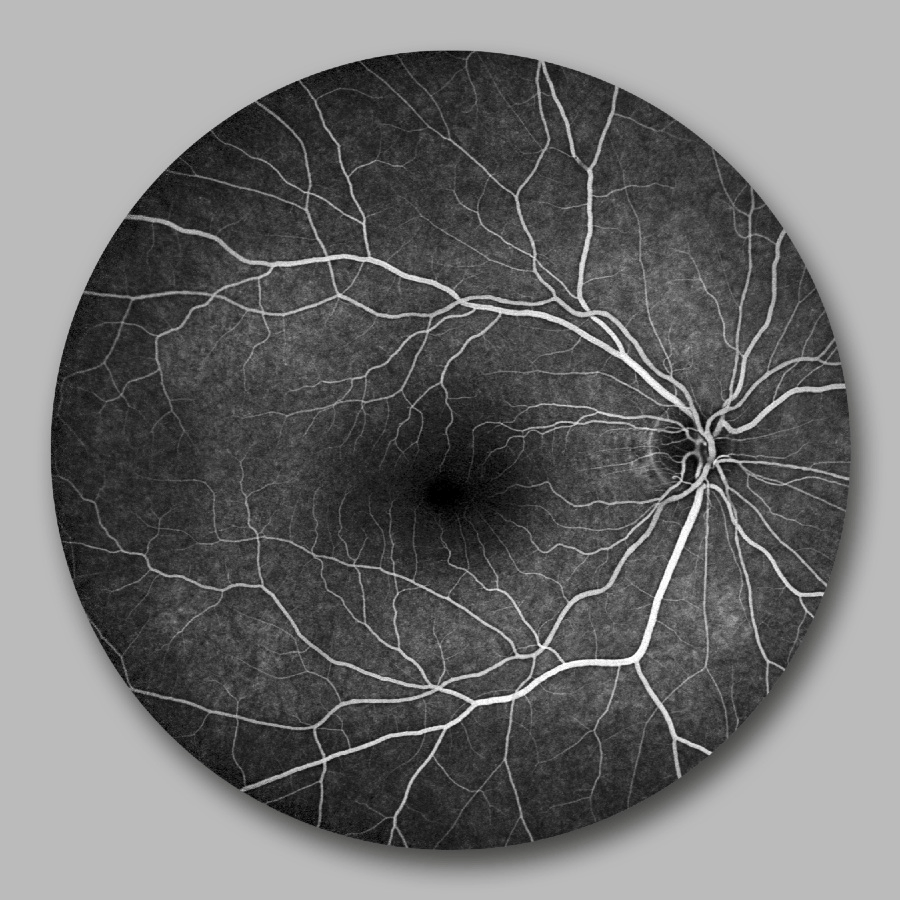

Die Fluoreszenzangiographie ist ein wichtiges Verfahren, um die Blutgefäße der Netzhaut sichtbar zu machen. Nach Injektion einer geringen Menge eines Farbstoffs in die Armvene verteilt sich dieser im Körper und erreicht innerhalb weniger Sekunden die Augen.

Mithilfe des Optomap Optos können wir den Farbstofffluss im Augenhintergrund hochauflösend und in einem besonders großen Blickfeld erfassen.

Dies stellt eine weitere diagnostische Möglichkeit dar, die wir mit dem Optos nutzen können. So lassen sich Durchblutungsstörungen, diabetische Veränderungen, Makuladegeneration oder Gefäßverschlüsse zuverlässig erkennen und dokumentieren.